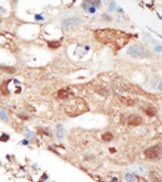

Supportive validation

- Submitted by

- OriGene (provider)

- Main image

- Experimental details

- Formalin-fixed and paraffin-embedded human cancer tissue reacted with the primary antibody, which was peroxidase-conjugated to the secondary antibody, followed by AEC staining.

- Validation comment

- IHC